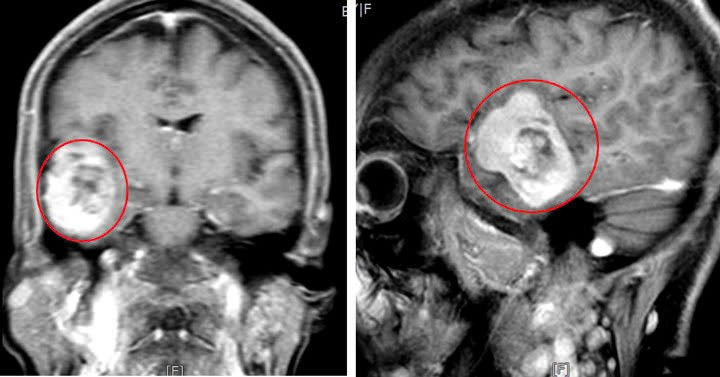

| Hình ảnh khối u của người bệnh. Ảnh BVCC |

Sau khi thăm khám và chụp cắt lớp vi tính, MRI phát hiện có khối u màng não lớn kích thước 5x4cm, khối u nằm ở vùng hố thái dương dính vào màng cứng. Các bác sĩ đã nhanh chóng tiến hành phẫu thuật vi phẫu bóc tách và loại bỏ khối u.